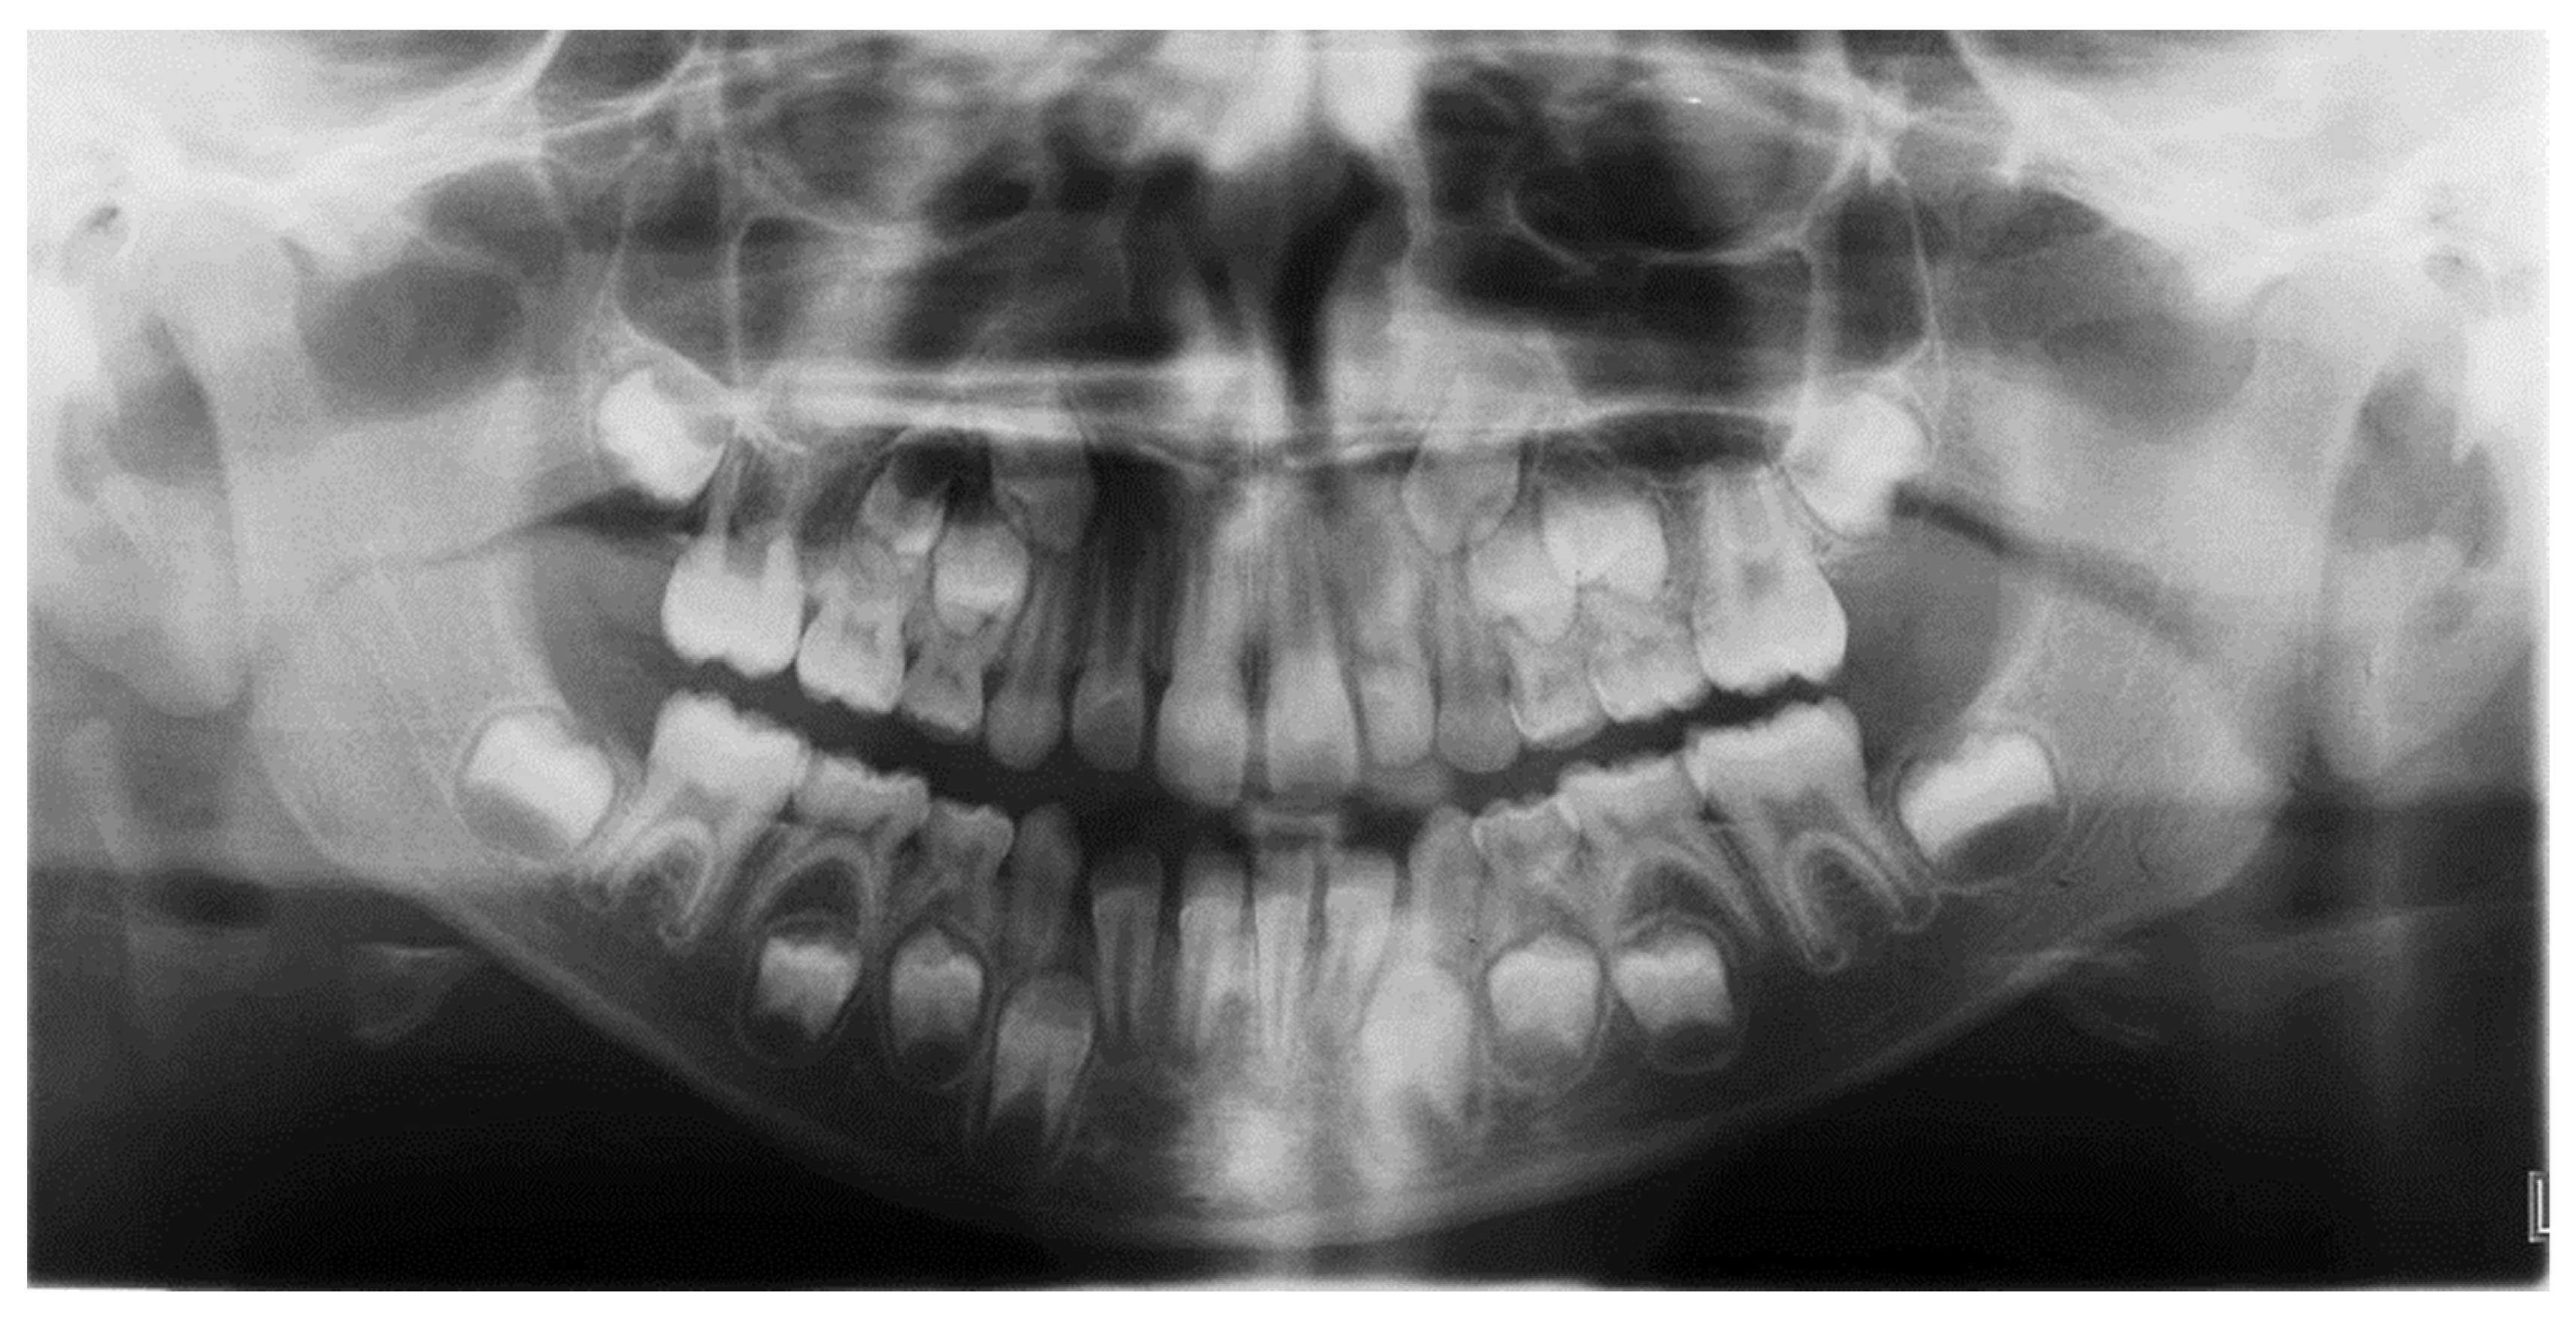

2. Materials and Methods

3. Results